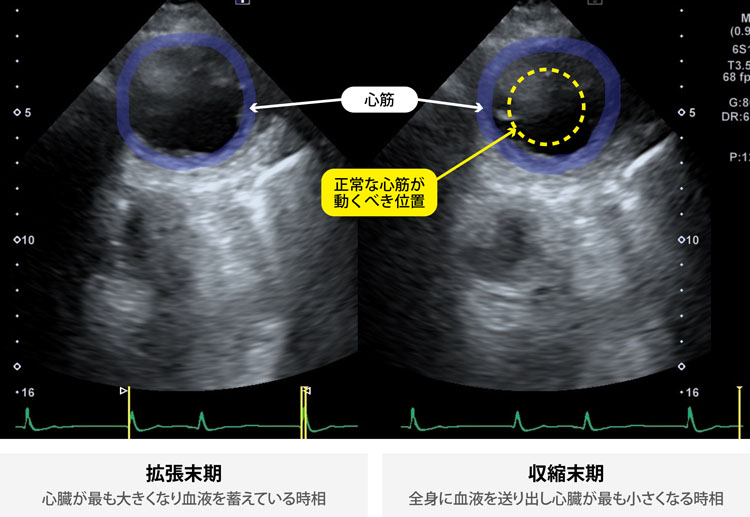

■心筋梗塞